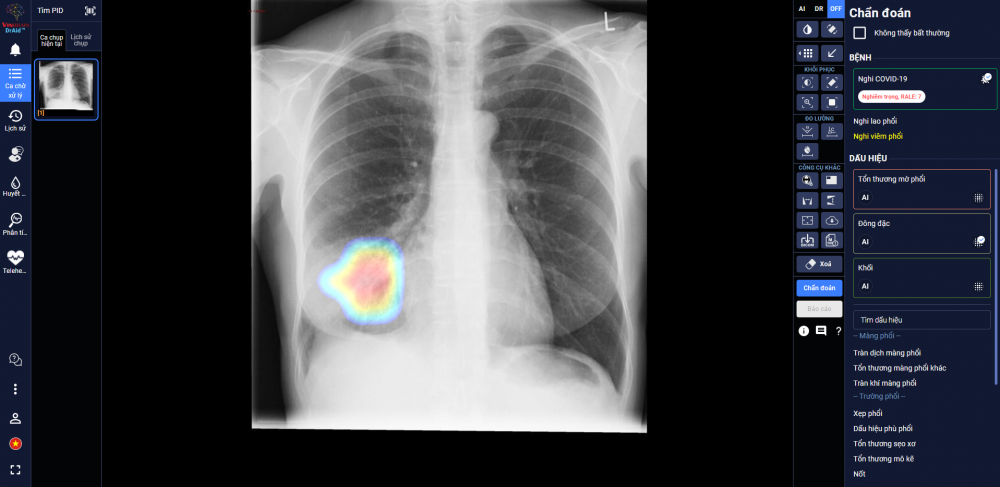

(LĐTĐ) DrAid cho Covid -19 - sản phẩm ứng dụng Trí tuệ nhân tạo (AI) của Công ty Cổ phần VinBrain (thuộc Tập đoàn Vingroup) – vừa được Hội đồng Khoa học Bộ Y tế nghiệm thu và đặc biệt kiến nghị nên sớm đưa vào sử dụng hàng ngày tại các bệnh viện trong giai đoạn Covid -19 đang tiếp tục lây lan như hiện nay. Đây được coi là một công cụ hỗ trợ sàng lọc và tiên lượng điều trị Covid -19 mới hữu hiệu, góp phần chủ động dự phòng và kiểm soát dịch hiệu quả.